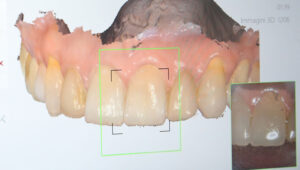

Resa estetica eccellente:

L’utilizzo di software di progettazione permettono di coinvolgere il paziente dall’inizio nelle fasi di progettazione, così da poter scegliere la migliore estetica possibile per riabilitare il suo caso.

Successivamente inizierà la fase di progettazione, dove un programma dedicato elaborerà tutti i dati acquisiti. Inoltre verra’ coinvolto il Tecnico, che svilupperà il progetto Protesico definitivo, da sottoporre ad approvazione del paziente prima dell’intervento